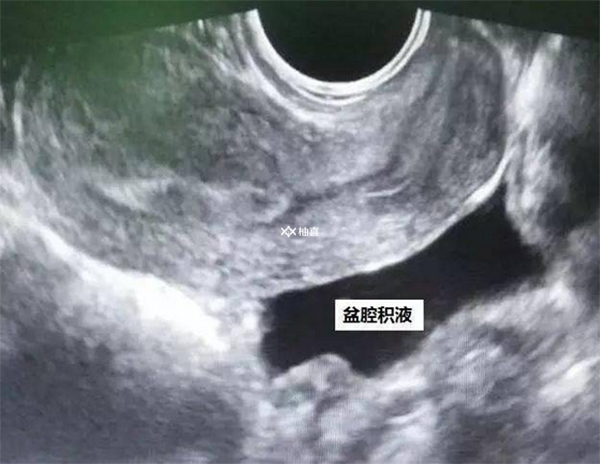

有盆腔积液能否移植取决于病情,如果只有少量积液那么就可以移植,因为大部分积液会自动被吸收,症状是下腹疼痛、腰酸不适等。一般来说,当盆腔积液小于5mm时,属于正常情况。如果大于5mm,属于脓性和血性渗液,且数量较多,则不能移植。如果是病理性盆腔积液,那么在移植前需要先进行治疗。